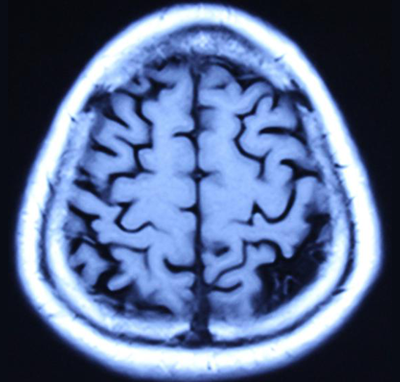

图1-1 (治疗前) 图1-2(治疗前)

图1-3 (治疗后) 图1-4(治疗后) 上图是严重脑萎缩用中药治疗半年核磁共振影像的前后对比:周先生 男 76岁 面无表情,意识不清,记忆严重减退二年余,肢体活动困难,病情渐渐加重,对自己名字不知道,自己吃的什么饭不清楚,不能自己行走等病情,临床诊断为:阿尔茨海默病(老年痴呆症),脑中风后遗症。2018-年02月06日磁共振影像显示:脑萎缩(图1-1、图1-2下端黑洞脑组织严重缺损)。经中药治疗半年,患者面部病情正常,意识恢复正常,对自己的名字及他人都清楚,吃过的食物过后也记得,能够与他人正常交流,能够自己行走活动。2018年8月3日核磁共振影像(图1-3、图1-4)显示:脑萎缩与2018年2月6日(图1-1、图1-2)比较脑萎缩明显恢复(脑组织严重黑洞缺损消失)。影像证明了:经治疗使的脑细胞再增长,使脑组织增多,使脑组织逆生长。 我们编著了《大脑复原理论 大脑细微结构修复术》(成了脑科研究的参考资料)以及近期编著了《大脑复原理论 大脑医疗技术探秘》,介绍了脑细胞再生长的原理和临床治疗成功的验证,是我们中国人在国际上首先提出了脑细胞再生长和成功做到了脑细胞再生长!我们对大脑萎缩、小脑萎缩、脑科疑难疾病的有效治疗,是用核磁共振进行治疗前后的对比。 2016年6月在中国海南博鳌召开的“2016世界医疗旅游和世界健康学术大会”和2016年7月在曼谷召开的“世界传统医学大会”上,贾学铭教授发表并介绍用纯中药使脑细胞再生长治疗脑萎缩、阿尔茨海默(老年痴呆症)能够治愈的效果,用核磁共振影像片子进行治疗前后的对比,证明脑组织有了新的增多,做到了使脑细胞再生长的效果,改变了过去医学界不可治愈的理论,受到了美国、德国、澳大利亚、意大利、英国、法国等参会的代表和许多国家专家的认可和赞扬。这个“脑细胞能够再生长”的理论,到目前是贾学铭教授和贾沅潽医学博士首先提出的,也是首先用影像证明能够做到的,为人类健康事业流出一定的贡献。 在党的十八大以来,为强我中华,创新中医、发展中医,创新做到了用中医中药的方法,艰难的创新再创新的实践,做到了脑细胞再生长、脑组织能够再生长,造福了脑科疑难病患者,脑细胞再生长,治疗了大量的脑萎缩病人。对脑科医学理论和脑科疑难病治疗有重要的参考意义。在国际上产生了很好的影响,显示了中国中医药的魁宝,2016年7月在曼谷召开的世界传统医学大会上获得了《世界传统医学突出贡献奖》和《世界传统医学终身成就奖》。对现在及往后的脑科研究和脑科疑难病的治疗有重要的意义,为国际脑科医学的研究和治疗做出了显著的贡献。 贾学铭教授,贾沅潽博士介绍: 贾学铭,字:瀚珺,教授, 主任医师,从事中医工作50年,资深中医专家,中医脑科专家,中国传统医学名医,中国名人俱乐部副主席兼健康委员会主任,中华中医药学会专家委员,英国中医师学会知名专家、中医顾问,中国生命关怀协会心脑血管病防治指导专家,山东潍坊吉缘堂抗衰老中医药研究所法人等职。北京同仁堂中医医院贵宾楼专家,北京同仁堂王府井中医院心脑血管病专家,301医院远程医学中心专家,301健康管家心脑血管病专家,北京八大处中西医结合医院脑科专家。 贾沅潽医学博士,国外留学10年,2012年回国,山东潍坊吉缘堂抗衰老中医药研究所所长等职。通过我们研究治疗的临床案例等研究,2015年编著了《大脑复原理论 大脑细微结构修复术》,2019年编著了《大脑复原理论 大脑医疗技术探秘》,介绍了脑细胞再生长的原理和治疗的成功验证,是我们中国人在国际上首先提出了脑细胞再生长和成功做到了脑细胞再生长!为脑科医学作出了非常有意义的贡献! |